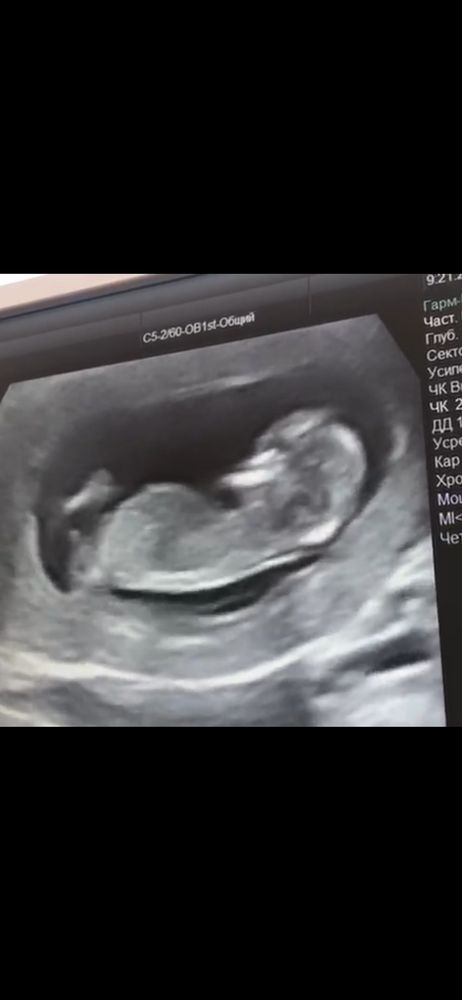

прикрепляю фото.. простите за качество, это скрин с видео)

первое фото это со скрининга 12 нед 2 дня